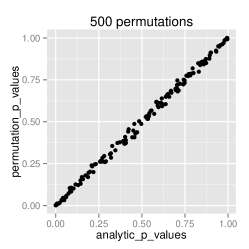

Analytical approximation of p-values

To confirm that the analytical approximation of null distribution of GDM is correct, we estimated the p-values through the approximation technique as well as through permutation testing. A range of 10 to 10,000 permutations was applied to observe the error rate. This experiment was performed on the ADNI dataset. The results displayed in figure 1 demonstrate that the analytic approximation holds with approximately error.